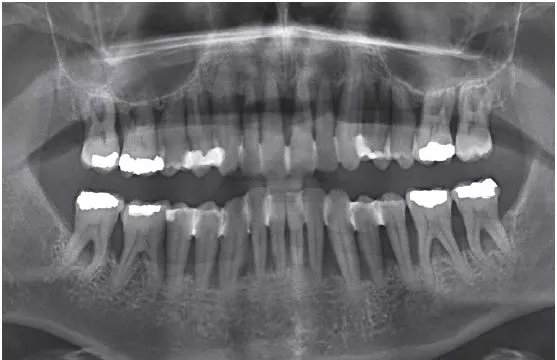

Der Patient (männlich, 48 Jahre alt) wurde im Jahr 2018 mit Verdacht auf aggressive Parodontitis (alte Nomenklatur) ins ZFZ Stuttgart überwiesen. Es bestanden keine Vorerkrankungen, keine familiären Auffälligkeiten und der Patient war Nichtraucher. Die Diagnose des überweisenden Zahnarztes konnte bestätigt werden.

Folgende klinische Befunde wurden eingangs erhoben: Plaqueindex (Ausgangssituation: QH 54%), Blutungsindex (Ausgangssituation: BOP 72%), Sondierungstiefen (Ausgangssituation: bis zu 10 mm – aus diesem Grund erfolgte eine teilweise Schienung) (Abb. 1).

Zunächst wurde eine nicht chirurgische Parodontitistherapie an allen Zähnen mit adjuvanter Antibiose („Winkelhoff-Cocktail“) durchgeführt. Nach 5 Monaten folgte eine offene PAR-Therapie im Seitenzahngebiet unter Einsatz von Emdogain®.

Ein Jahr nach Abschluss der aktiven Phase zeichnet sich eine positive Entwicklung ab. Die Sondierungstiefen sind deutlich reduziert (< 7 mm); deutliche Verbesserungen wurden bezüglich der Blutung (BOP 35%) und der Belagsbildung (QH 27%) registriert (Abb. 2a–c).